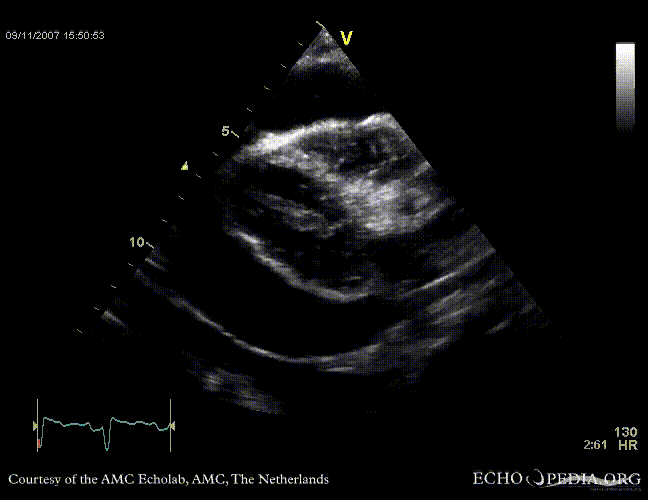

Tamponade

Courtesy of:

J. Vleugels, AMC, The Netherlands

tamponade 4